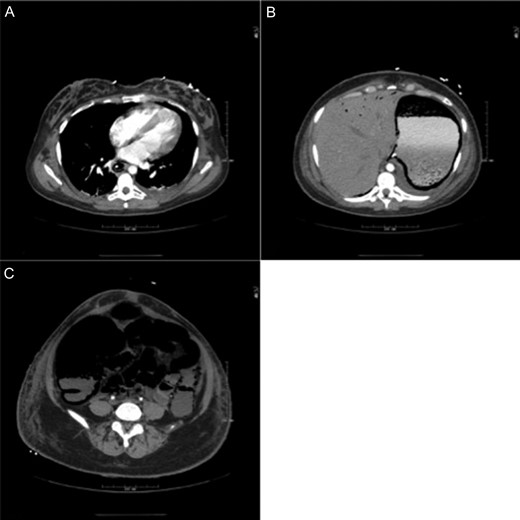

After a post-operative ileus, enteral feeds were restarted on PBD 15 (post-bowel resection Day 11). A CT on PBD 19 for infectious work-up demonstrated resolution of pneumatosis and HPVG (Fig. 6). Excision of the burn wounds began on PBD 4 and was complete on PBD 50. The patient was discharged 2 months after burn injury. At the time of discharge, she had a functioning ileostomy and was tolerating an oral diet with appropriate nutritional parameters. She continues to recover well after her burn surgeries.

CT scan obtained on post-burn Day 19 demonstrating resolution of pneumatosis and hepatic portal venous gas.